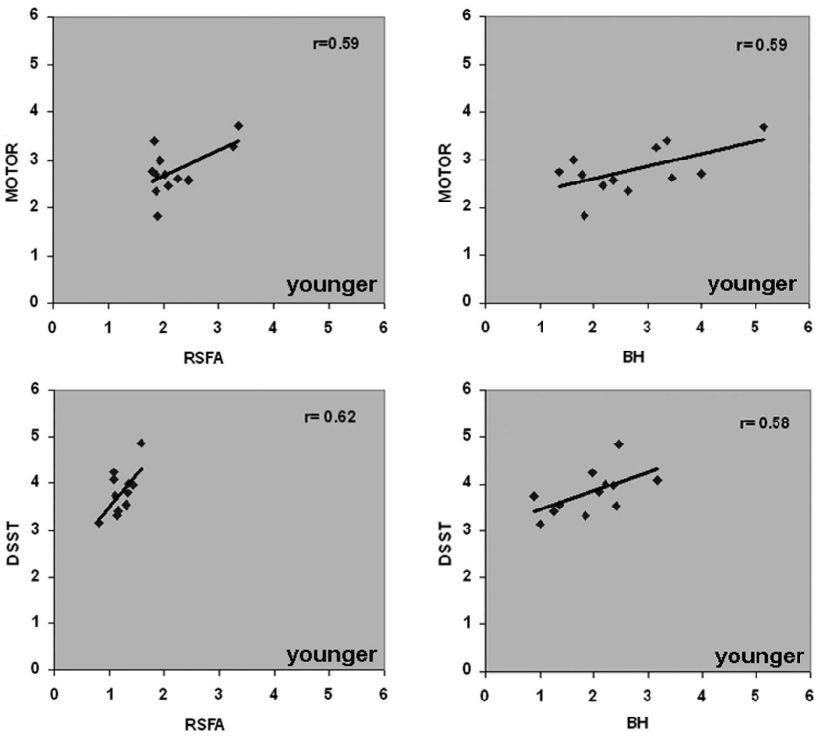

An alternative estimation of CVR (?)

Text

[Zou et al. 2013 (Hum. Brain Mapp.)]

[Kannurpatti et al. 2014 (PLoS ONE)]

[Mennes et al. 2011 (NeuroImage)]

Results: CVR and RSF

Physiology and RSF

We used 3dLMEr¹ to set up the following LME models (R syntax):

Effect of Sex

Only sex had a significant effect on RSF

Effect on CVR

Results: CVR and RSF

Golestani et al. 2016 (NeuroImage)

Results: CVR, RSF, and tasks

The relationship between CVR, RS fluctuations, and tIA

might be highly subject specific

or absent altogether.